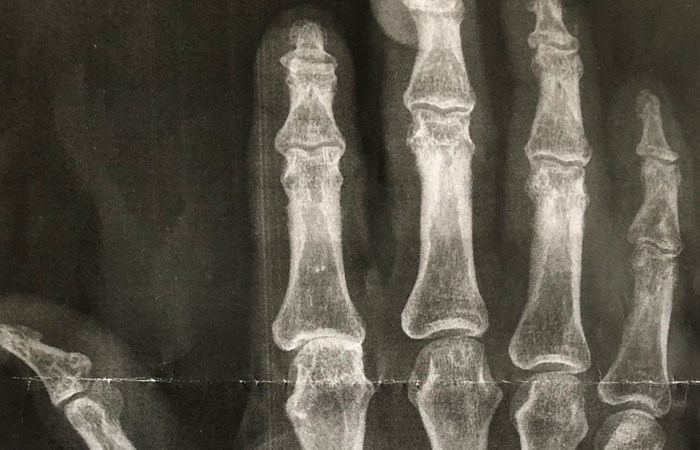

För att få fram resultatet har forskarna jämfört röntgenbilder på händer med metabola parametrar som övervikt/bukfetma, högt blodtryck, insulinresistens och blodfettsrubbningar på 310 personer.